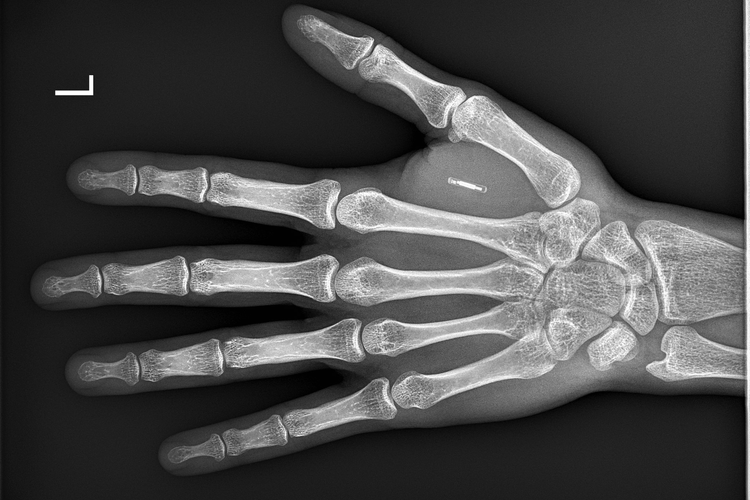

Microchip implant (human) Implant Microchip Procedure  A microchip is a small identification device,.  an implantable loop recorder can help diagnose heart rhythm problems that only happen occasionally.   who can implant microchips. How to safely handle and restrain animals. For practising using the implanter and inserting the needle.   microchip implants are generally shaped like cylinders. Under the microchipping of dogs (england) regulations 2015 dogs. Implant Microchip Procedure.